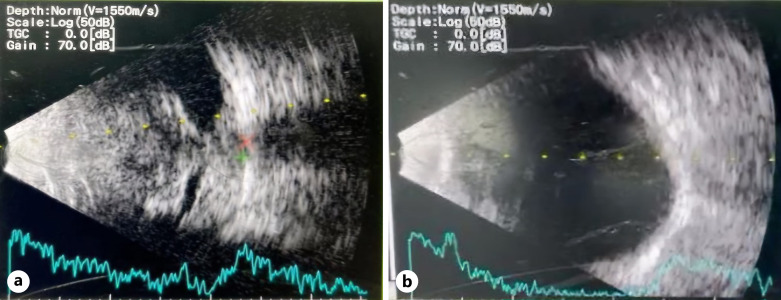

Case presentation: An Indonesian male, 38 years old, complained of vision loss and ocular pain in his right eye 1 month ago. The pain frequently manifests as a rapid, piercing, or scorching feeling that extends from the right eye to encompass the entire head. Both of his eyes exhibited symblepharon and xerophthalmia. At the age of 11, he experienced a previous occurrence of raised and blister-like skin lesions. Following his recovery, a gradual formation of membranes occurred, covering both of his eyes. His right eye had light perception for visual acuity, and the intraocular pressure was determined to be soft upon examination. The B-scan ultrasound revealed the presence of a long-term inflammatory or scarring process and a decrease in the length of the axis. The patient underwent surgery without experiencing any improvement. A psychological evaluation identified a headache caused by an eye condition, and we administered antipyretic, anticonvulsant, antidepressant, and multivitamin treatments. The patient saw a reduction in pain intensity from a level of 9 to 5 after undergoing treatment for a duration of 1 week. Patients who have previously undergone surgical treatment for symblepharon should have a comprehensive evaluation when they encounter symptoms of vision loss and ocular discomfort.